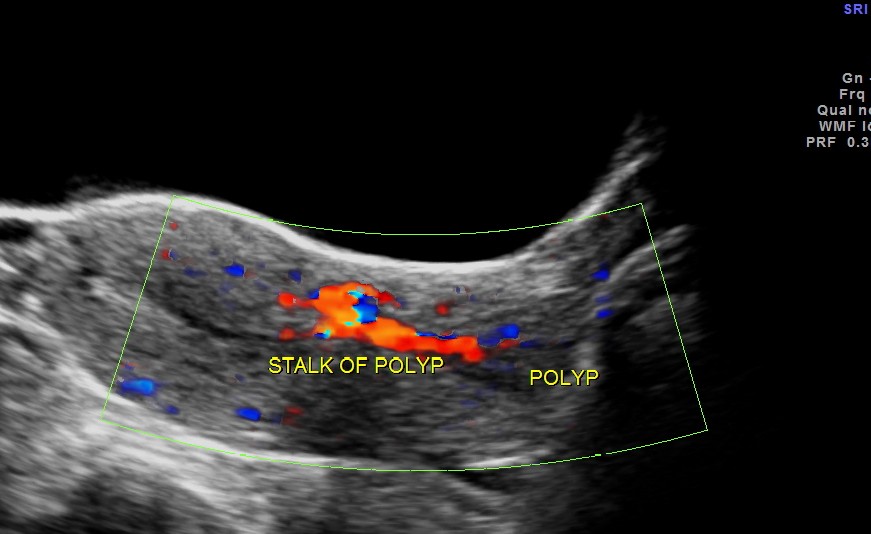

the following images are acquired trans vaginally and the starking difference in clarity can be appreciated.

the multi planar 3 d image shows increased flow in the polyp and the stalk arising from the endometrium

The diagnosis offered was an endometrial polyp with a long stalk situated in the cervix.